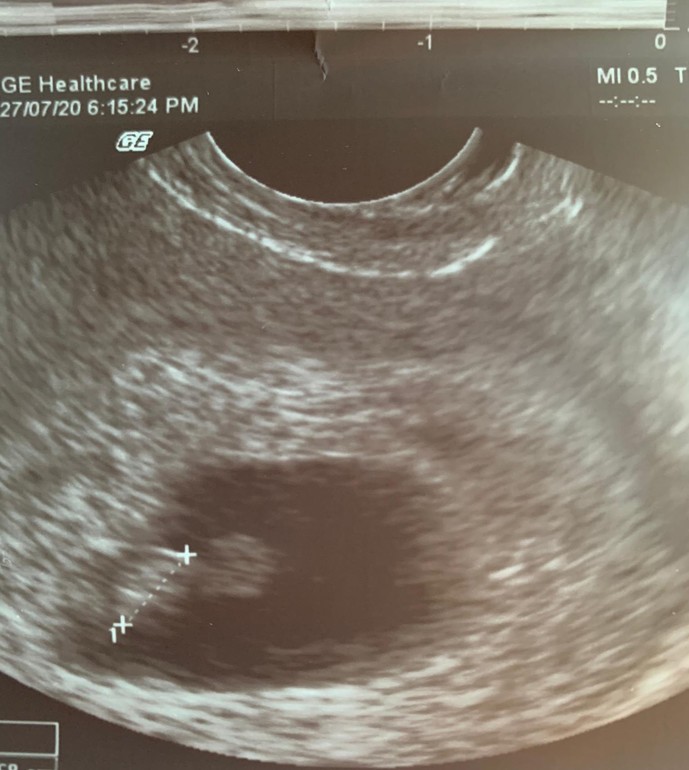

Первое узи, 7 недель и 2 дня

УЗИ, КТГ, доплерНу вот и сходила я на первое узи, крошку нашли, ЖМ есть, СБ есть (правда не посчитали сколько ударов в минуту, странно конечно, ну ладно). Врач сказала, что все соответсвует сроку, хотя меня немного напрягает размер КТР - 7 мм, несмотря на мою позднюю О (на 17 дц), вижу что по таблицам остаем на день-два, и теперь я места себе не нахожу. Девочки, как думаете, это очень критично или может еще догонит?

А эмбриончик это то, что на узи отмечено пунктиром?

Да, эмбрион это то что пунктиром, это он 7 мм, а тот кружочек рядом это ЖМ, я тоже думала что это голова 😅